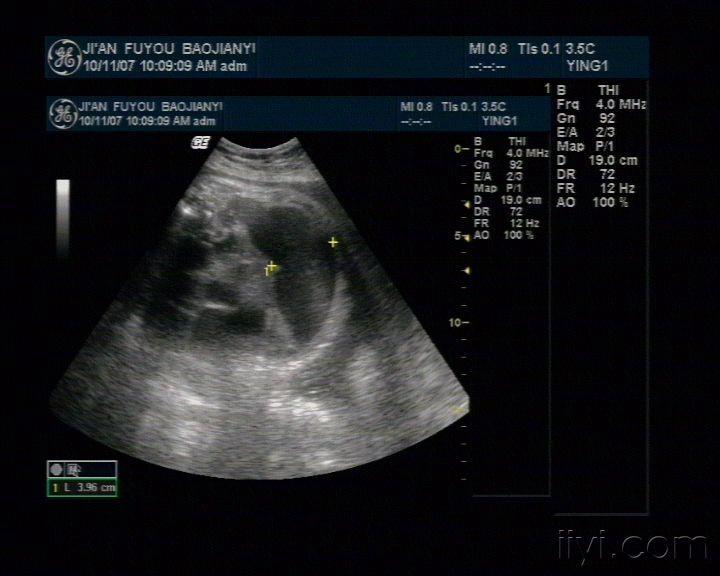

肠梗阻超声图像表现为肠腔扩张,达4cm,不蠕动.9.

图片尺寸3120x4160